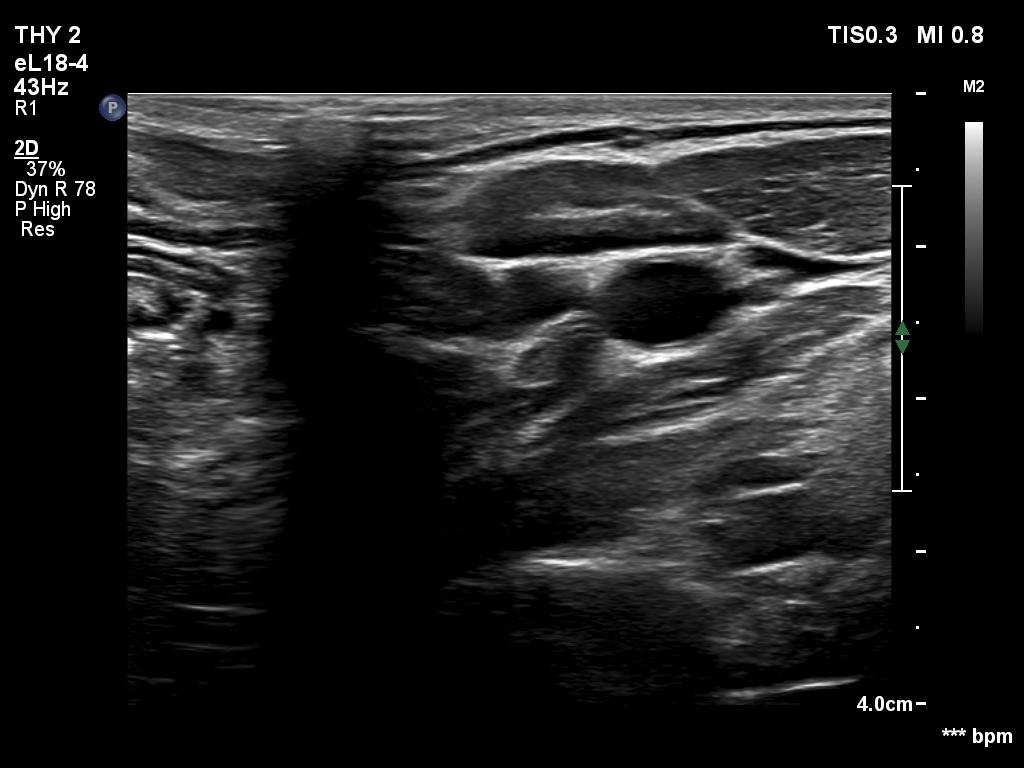

Ultrasonography. The thyroid was echonormal. There was a discrete, minimally hypoechoic area in the dorsal part of the right lobe. This was a technical artifact, caused by a connective tissue band crossing the thyroid. Although on transverse scan, the lesion looked deceptively as a discrete lesion, the real situation became clear on longitudinal scan.

The area in question did not correspond to a discrete lesion. It seemed to be circumscribed because of the presence of connective tissue running ventral which hindered the penetrance of ultrasound wave, therefore made the dorsal area hypoechoic.